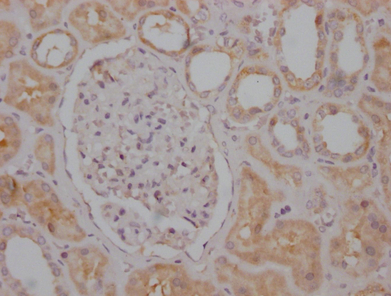

IHC圖像說明:

RPTOR重組單克隆抗體[1B10]稀釋比例為1:100,用于染色石蠟包埋的人腎組織,實(shí)驗在Leica Bond系統(tǒng)上完成。經(jīng)過脫蠟和水化后,使用檸檬酸緩沖液(pH 6.0)通過高壓進(jìn)行抗原修復(fù)。切片用10%正常山羊血清封閉30分鐘。然后將一抗(含1% BSA)在4℃孵育過夜。一抗通過抗兔IgG聚合物(標(biāo)記有HRP)檢測。